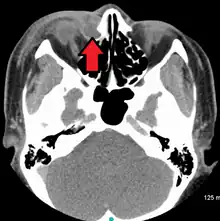

| A case of dacryocystitis as seen on CT scan | |